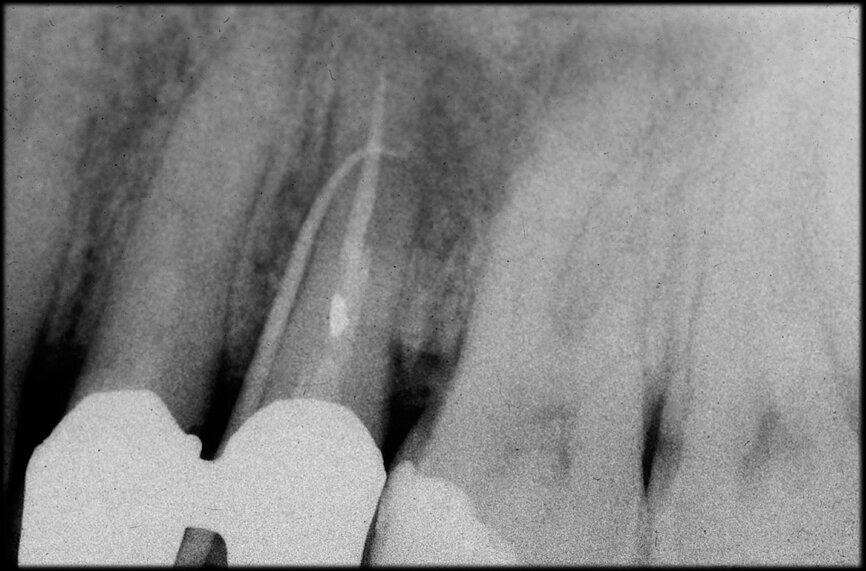

In the maxillary premolar shown in Figures 5 and 6, the fistulogram revealed the presence of an apical lesion that extended coronally to approximately the middle third of the root. The clinical decision could, therefore, propend towards orthograde retreatment; however, CBCT gave us a very different view of the situation compared with the radiograph, as it indicated that a prior treatment had irreversibly damaged the tooth, which would therefore have to be extracted.